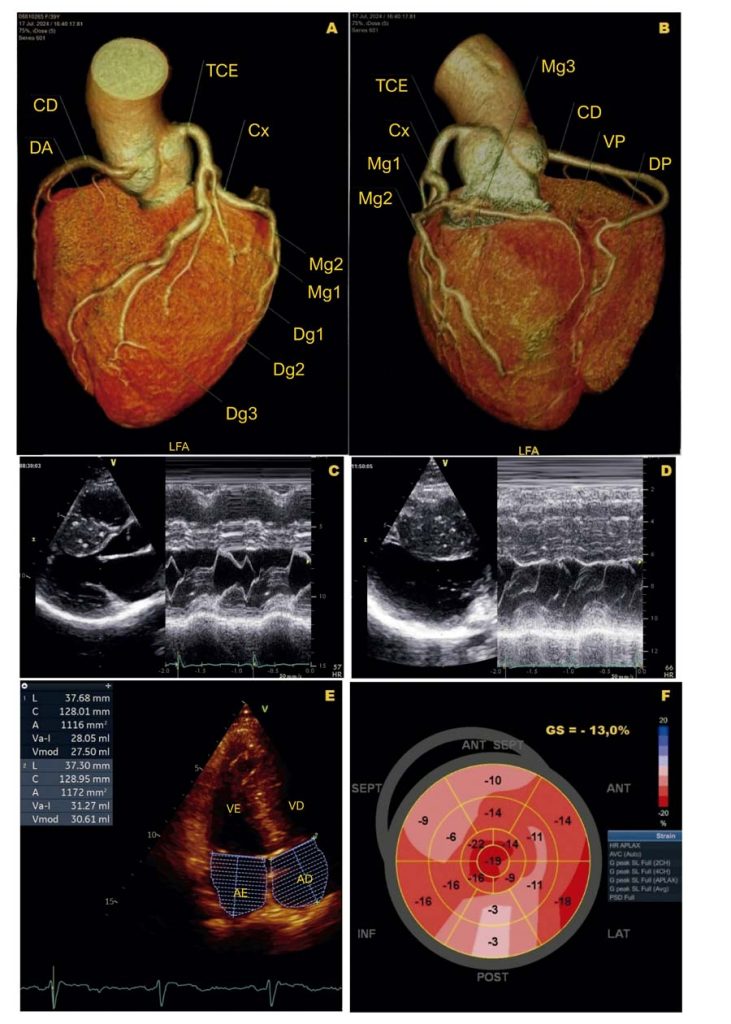

Paciente com cardiomiopatia hipertrófica (CMH) grave e sintomática, sem gradiente expressivo na via de saída do ventrículo esquerdo (VSVE) em repouso, requer avaliação adicional. Durante o ecocardiograma sob esforço (EE) em bicicleta supina, uma obstrução dinâmica subestimada ou latente pode ser identificada em tempo real, sendo particularmente relevante a avaliação em condição pós-prandial.